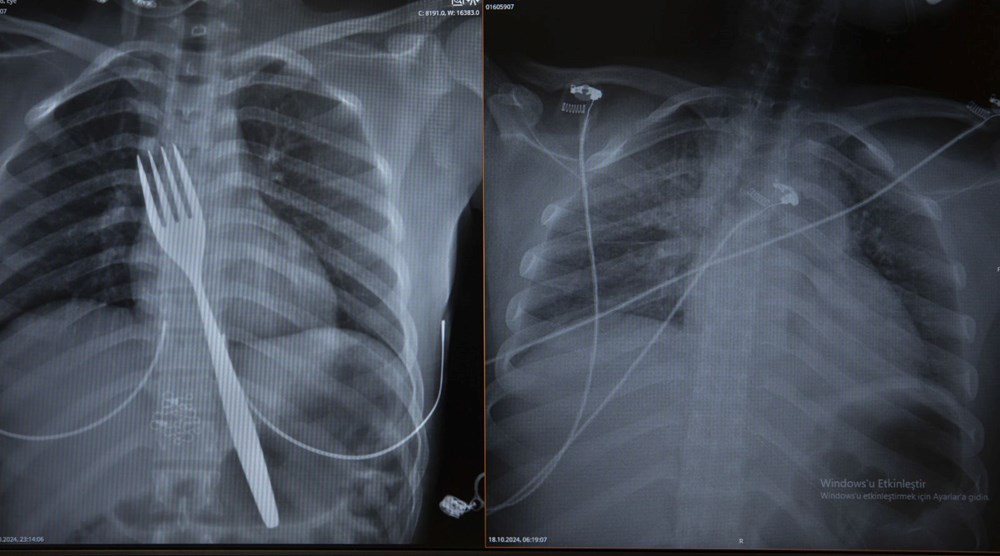

Burada röntgeni çekilen hastanın yemek borusunda 18 santimlik çatal olduğu tespit edildi.

Vakayı ilk duyduğunda şaşırdığını anlatan Edizsoy, "Büyük bir çatalın tamamen yutulması şeklinde ortaya çıkan bu vakayı ilk duyduğumda doğru olmadığını düşündüm. Hasta 18 yaşında ve yabancı uyrukluydu. Türkçesi biraz zayıf olduğu için belki de yanlış anlaşılmalar olabileceğini düşündük. Ama hastanın filmini çektiğimizde gerçekten bir çatalın yemek borusunda olduğunu gördük." dedi.